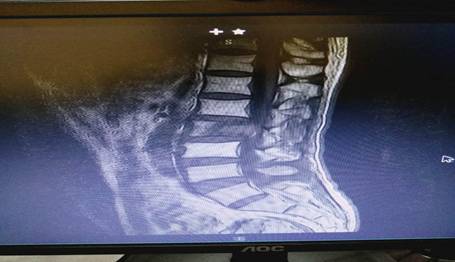

患者劉先生,54歲,患肝癌16個月,因腰腿痛伴下肢麻木4月余入住中心醫(yī)院脊柱外科。腰椎MRI顯示腰2椎體轉(zhuǎn)移腫瘤、椎管占位、神經(jīng)根受壓,PECT顯示腫瘤單節(jié)段椎體侵犯、椎弓根骨折。手術(shù)指針明顯。為最大限度地挽救患者的神經(jīng)功能,改善其生活質(zhì)量,脊柱外科決定為其施行手術(shù)切除減壓。術(shù)前,蘇光輝、汪向東二位主任帶領(lǐng)科室技術(shù)骨干與腫瘤科尹忠文主任、血管外科涂宏主任、麻醉科段雪琴主任多次會商術(shù)前計劃,經(jīng)周密術(shù)前準(zhǔn)備后,術(shù)前當(dāng)天由血管外科先行瘤體血管栓塞術(shù),以減少術(shù)中出血,栓塞手術(shù)非常成功,手術(shù)按時進行。術(shù)中蘇光輝主任、汪向東副主任與肖華斌、陳威副主任醫(yī)師為其施行腫瘤椎體全切術(shù)。術(shù)中出血量在2000ml以內(nèi),出血量的控制超出手術(shù)團隊的預(yù)期。手術(shù)相當(dāng)順利,術(shù)后患者快速康復(fù)出院。

術(shù)前腰椎MRI 圖片